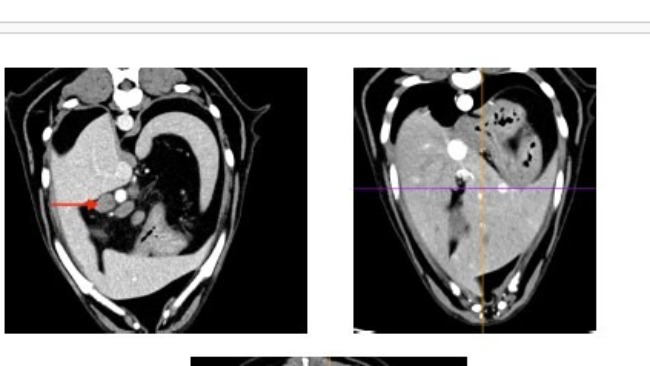

Pomimo początkowych wątpliwości szersze badania potwierdziły chłoniaka T-komórkowego.

Zwykłe badanie profilaktyczne, a wyszło: podniesiony kortyzol, powiększone węzły chłonne, pobudzona śledziona i płyn w jamie opłucnowej.

Badania moczu, badanie krwi, USG jamy brzusznej, echo serca, rtg, wizyta onkologiczna.... To wszystko co już mamy za sobą i nadal nie wiadomo co się z Atenką dzieje i nie wiadomo jak ją leczyć. Wykluczony został zespół Cushinga. Wykluczone zostały choroby serca. Podejrzenie chłoniaka na razie nie zostało potwierdzone. Diagnostyka trwa dalej, a koszty rosną w przerażającym tempie. Przed nami tomografia oraz biopsja śledziony, biopsje węzłów chłonnych, badanie cytologiczne płynu z jamy opłucnej. To koszt minimum 3000 zł.